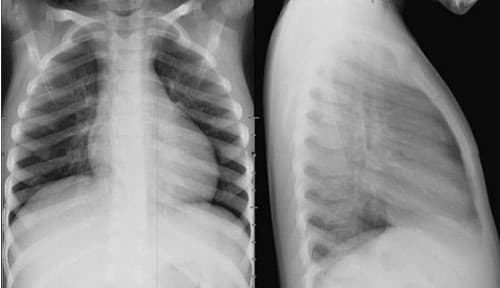

Chụp X quang phổi bao nhiêu tiền? Cần lưu ý những gì?

Chụp X quang phổi là một chẩn đoán hình ảnh quan trọng để chẩn đoán các bệnh lý về phổi. Vậy chụp X quang cùng phổi bao nhiêu tiền và cần lưu ý những gì? Bài viết dưới đây sẽ giúp bạn giải đáp cụ thể. 1. Vai trò chụp X quang trong chẩn đoán […]